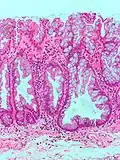

| Hyperplastic polyp of the stomach | Stomach | Elongated, tortuous, and cystic foveolae separated by edematous and inflamed stroma.[14] | ![]() |